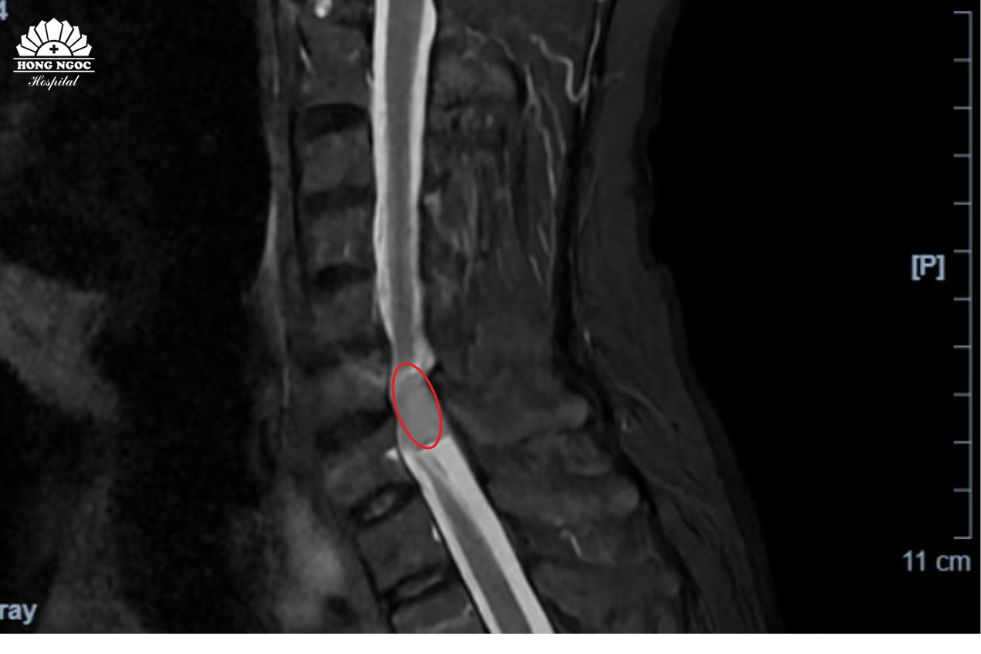

Trực tiếp thăm khám cho bệnh nhân, PGS.TS.BS Hà Kim Trung (Chuyên gia hơn 30 năm phẫu thuật thần kinh, cột sống - BVĐK Hồng Ngọc) chia sẻ: “U màng tủy cổ là bệnh lý hiếm gặp với các biểu hiện không rõ ràng, dễ nhầm lẫn với các triệu chứng của thoái hóa, thoát vị đĩa đệm cột sống. Kết quả chụp MRI cho thấy khối u đã chèn ép 1/2 ống tủy, khiến bệnh nhân có biểu hiện tê bì - yếu tứ chi. Đây là khối u lành tính, bởi vị trí u nằm ngoài tủy sống, không xâm lấn vào các tổ chức, cấu trúc xung quanh. Mục đích ca phẫu thuật loại bỏ khối u giúp giải phóng chèn ép, giảm tê bì, ngăn ngừa biến chứng mất cảm giác, liệt vận động cho người bệnh”.